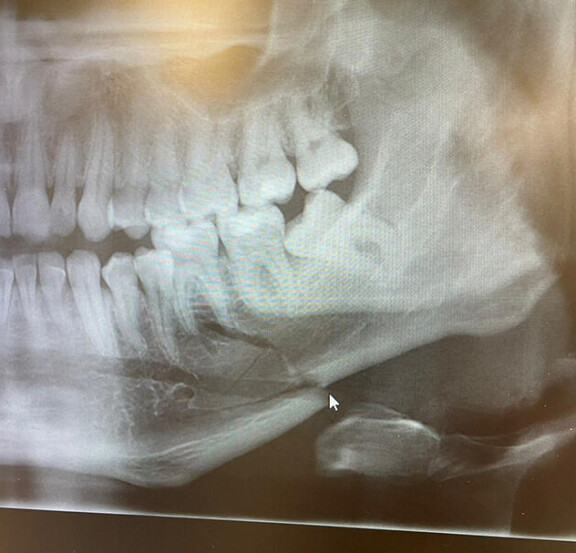

Mikan toipuminen on edelleen kesken, sillä leukaluu meni täysin poikki.

– Voi mennä jopa kesäkuuhun asti, että murtuma luutuu vahvaksi luuksi, hän sanoo.

Mikan leukaan on asennettu levyt, jotka tukevat leukaa murtuman parantumisen aikana.